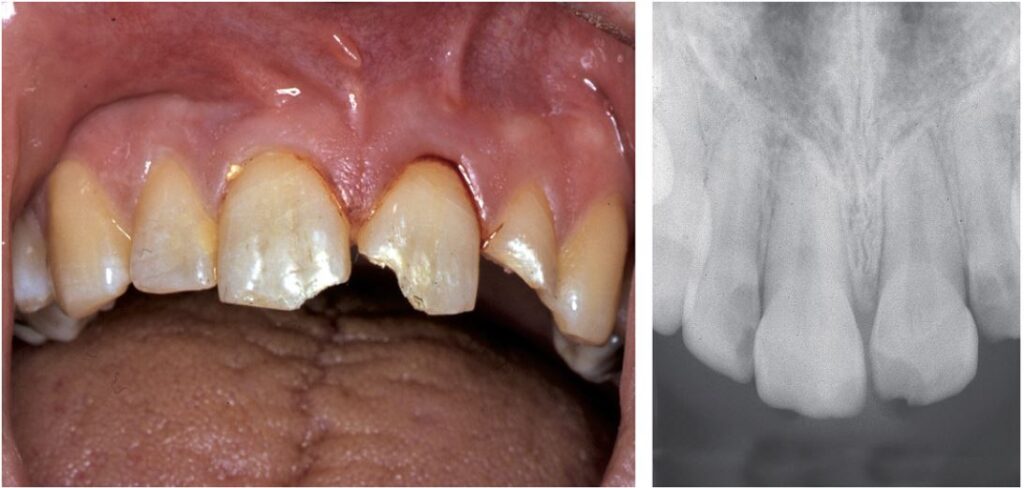

Gãy men và gãy men-ngà không liên quan đến tủy xảy ra thường xuyên ở cả răng sữa và răng vĩnh viễn. Chúng thường chỉ giới hạn ở một răng duy nhất, thường là các răng cửa giữa hàm trên. đặc biệt là các góc gần hoặc xa (Hình 13.3).

Đường gãy có thể nằm ngang theo chiều gần xa. Đôi khi chỉ liên quan đến thùy giữa của rìa cắn (Hình 13.4).

Trong một số ít trường hợp, đường gãy có thể ảnh hưởng đến toàn bộ bề mặt men răng mặt ngoài.